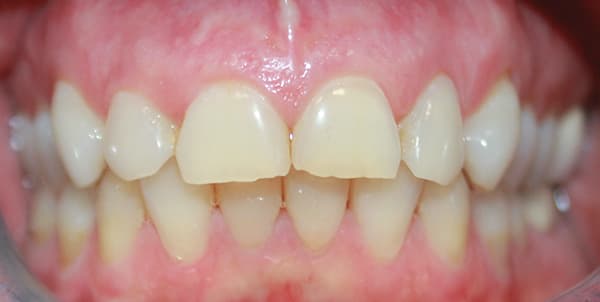

A female patient aged 57 years presented with altered passive eruption of the maxillary anterior teeth, which was diagnosed as a secondary condition to tooth erosion resulting from long-standing gastroesophageal reflux disease (GERD). Clear aligner therapy was initiated to level and align the occlusion and intrude the maxillary anterior teeth back to their original gingival position. After 18 months of poor patient compliance, improvement in tooth position was minimal and the amount of clinical overjet that was desired was not achieved. This limited the restorative armamentarium, and a decision was made to proceed with monolithic zirconia-oxide restorations. Following teeth preparation and tissue retraction, the case was impressed using an intraoral scanner (iTero® Element 2, Align Technology, Inc., itero.com). The final restorations were made of zirconium dioxide with a feldspar veneering ceramic shade 1M1 as the pressed layer on porcelain on the facials. The outcome of the case met the patient's primary concerns, achieving the lengthening and lightening of the anterior teeth that she desired. Because of the patient's continued challenges with GERD, however, she reported having difficulty with compliance related to the clear aligner therapy and whitening protocols, precluding a more ideal result. Nonetheless, the patient was pleased with her new smile and the clinician, given the challenging circumstances, was satisfied with the clinical results of the final restorations.